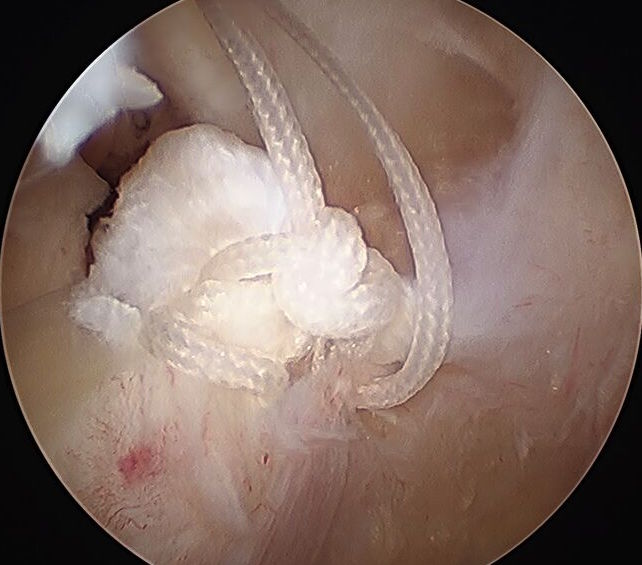

1. Suture anchor repair

- posterior compartment cannula

- insert cannula into posterior tibial plateau

- pass sutures and tie

- pass sutures through meniscal root (either labral suture passer or rotator cuff suture passer)

- retrieve through tunnel with houston suture passer

- tie over endobutton